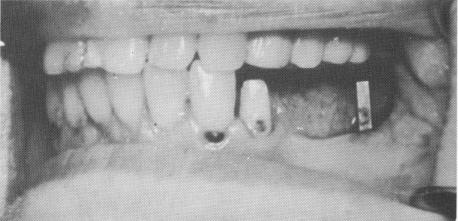

Fig. 14-41. Cavities developing underneath crowns that support fixed dentures also lead to eventual loss of the bridge as a result of cement seal leakage that loosens the prosthesis, thereby increasing the load on the implants and resulting in their eventual mobility. Here are seen two triplants and a vent-plant pulled out of the mouth still attached to the bridge.

Fig. 14-42. Any hard cement left underneath crowns covering implants can cause irritation of the soft tissue, which can lead to bone resorption.